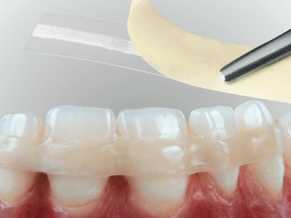

1) Стекловолокно. Это несъемный метод шинирования, к которому обращаться стали сравнительно недавно. Но на сегодня он очень популярен у пациентов, благодаря многим преимуществам. Стекловолокно в шинировании позволяет сохранить даже сильно расшатанные зубы, при этом почти не страдает их целостность.То есть, зубы не обтачивают и не депульпируют. Стекловолоконная шина не мешает гигиеническим процедурам, равномерно распределяет жевательную нагрузку между фиксированными зубами и отличается высокими эстетическими показателями.

Шинирование с помощью стекловолокна осуществляется в стоматологическом кабинете за один прием. Пациенту проводят местное обезболивание. Вдоль подвижных зубов, на внутренней стороне ряда на глубину 0,5 мм, проделывается бороздка для стекловолоконной нити, которая после укладки закрывается светоотверждаемым пломбировочным материалом. Свет превращает в балку композит со стекловолоконной нитью, благодаря которой зубы сцепливаются неподвижно вместе. Ответственный пациент, внимательно ухаживающий за полостью рта и следующий абсолютно всем советам стоматолога, может рассчитывать на 3-летний срок службы стекловолоконной шины. При этом ему нужно будет раз в год приходить к своему стоматологу для полировки конструкции. Не стоит шинировать передние зубы, если отсутствуют задние. Конструкция может сломаться из-за избыточной жевательной нагрузки на шинированный зубной ряд. Поэтому перед процедурой стекловолоконного шинирования необходимо навести порядок с прикусом и запротезировать недостающие зубные единицы.

Стекловолоконное шинирование зубов это один из самых эстетичных и надежных методов.

Стекловолокно сохраняет даже сильно расшатанные зубы. С его помощью можно легко убрать зубные промежутки.

Для проведения шинирования стекловолокном не требуется обтачивать зубы и так же удалять из них нерв. Все это дает минимальное травмирование ротовой полости.